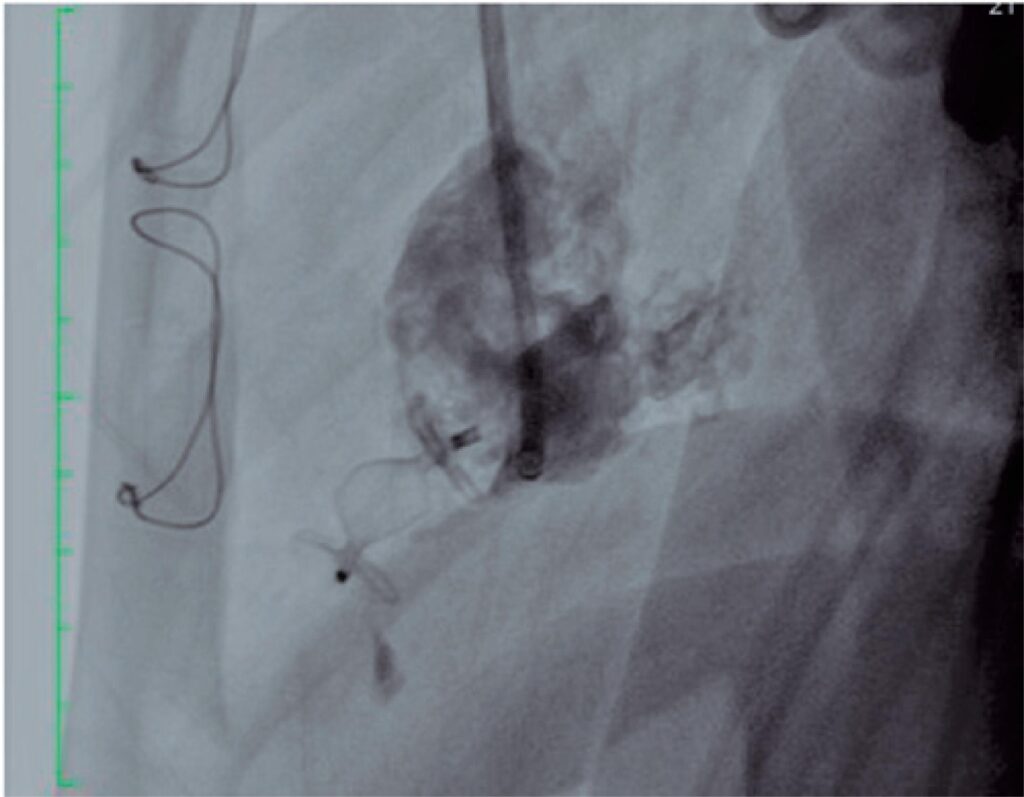

Figure 3

Control angiography images showing the device in position with occlusion of the diverticulum.